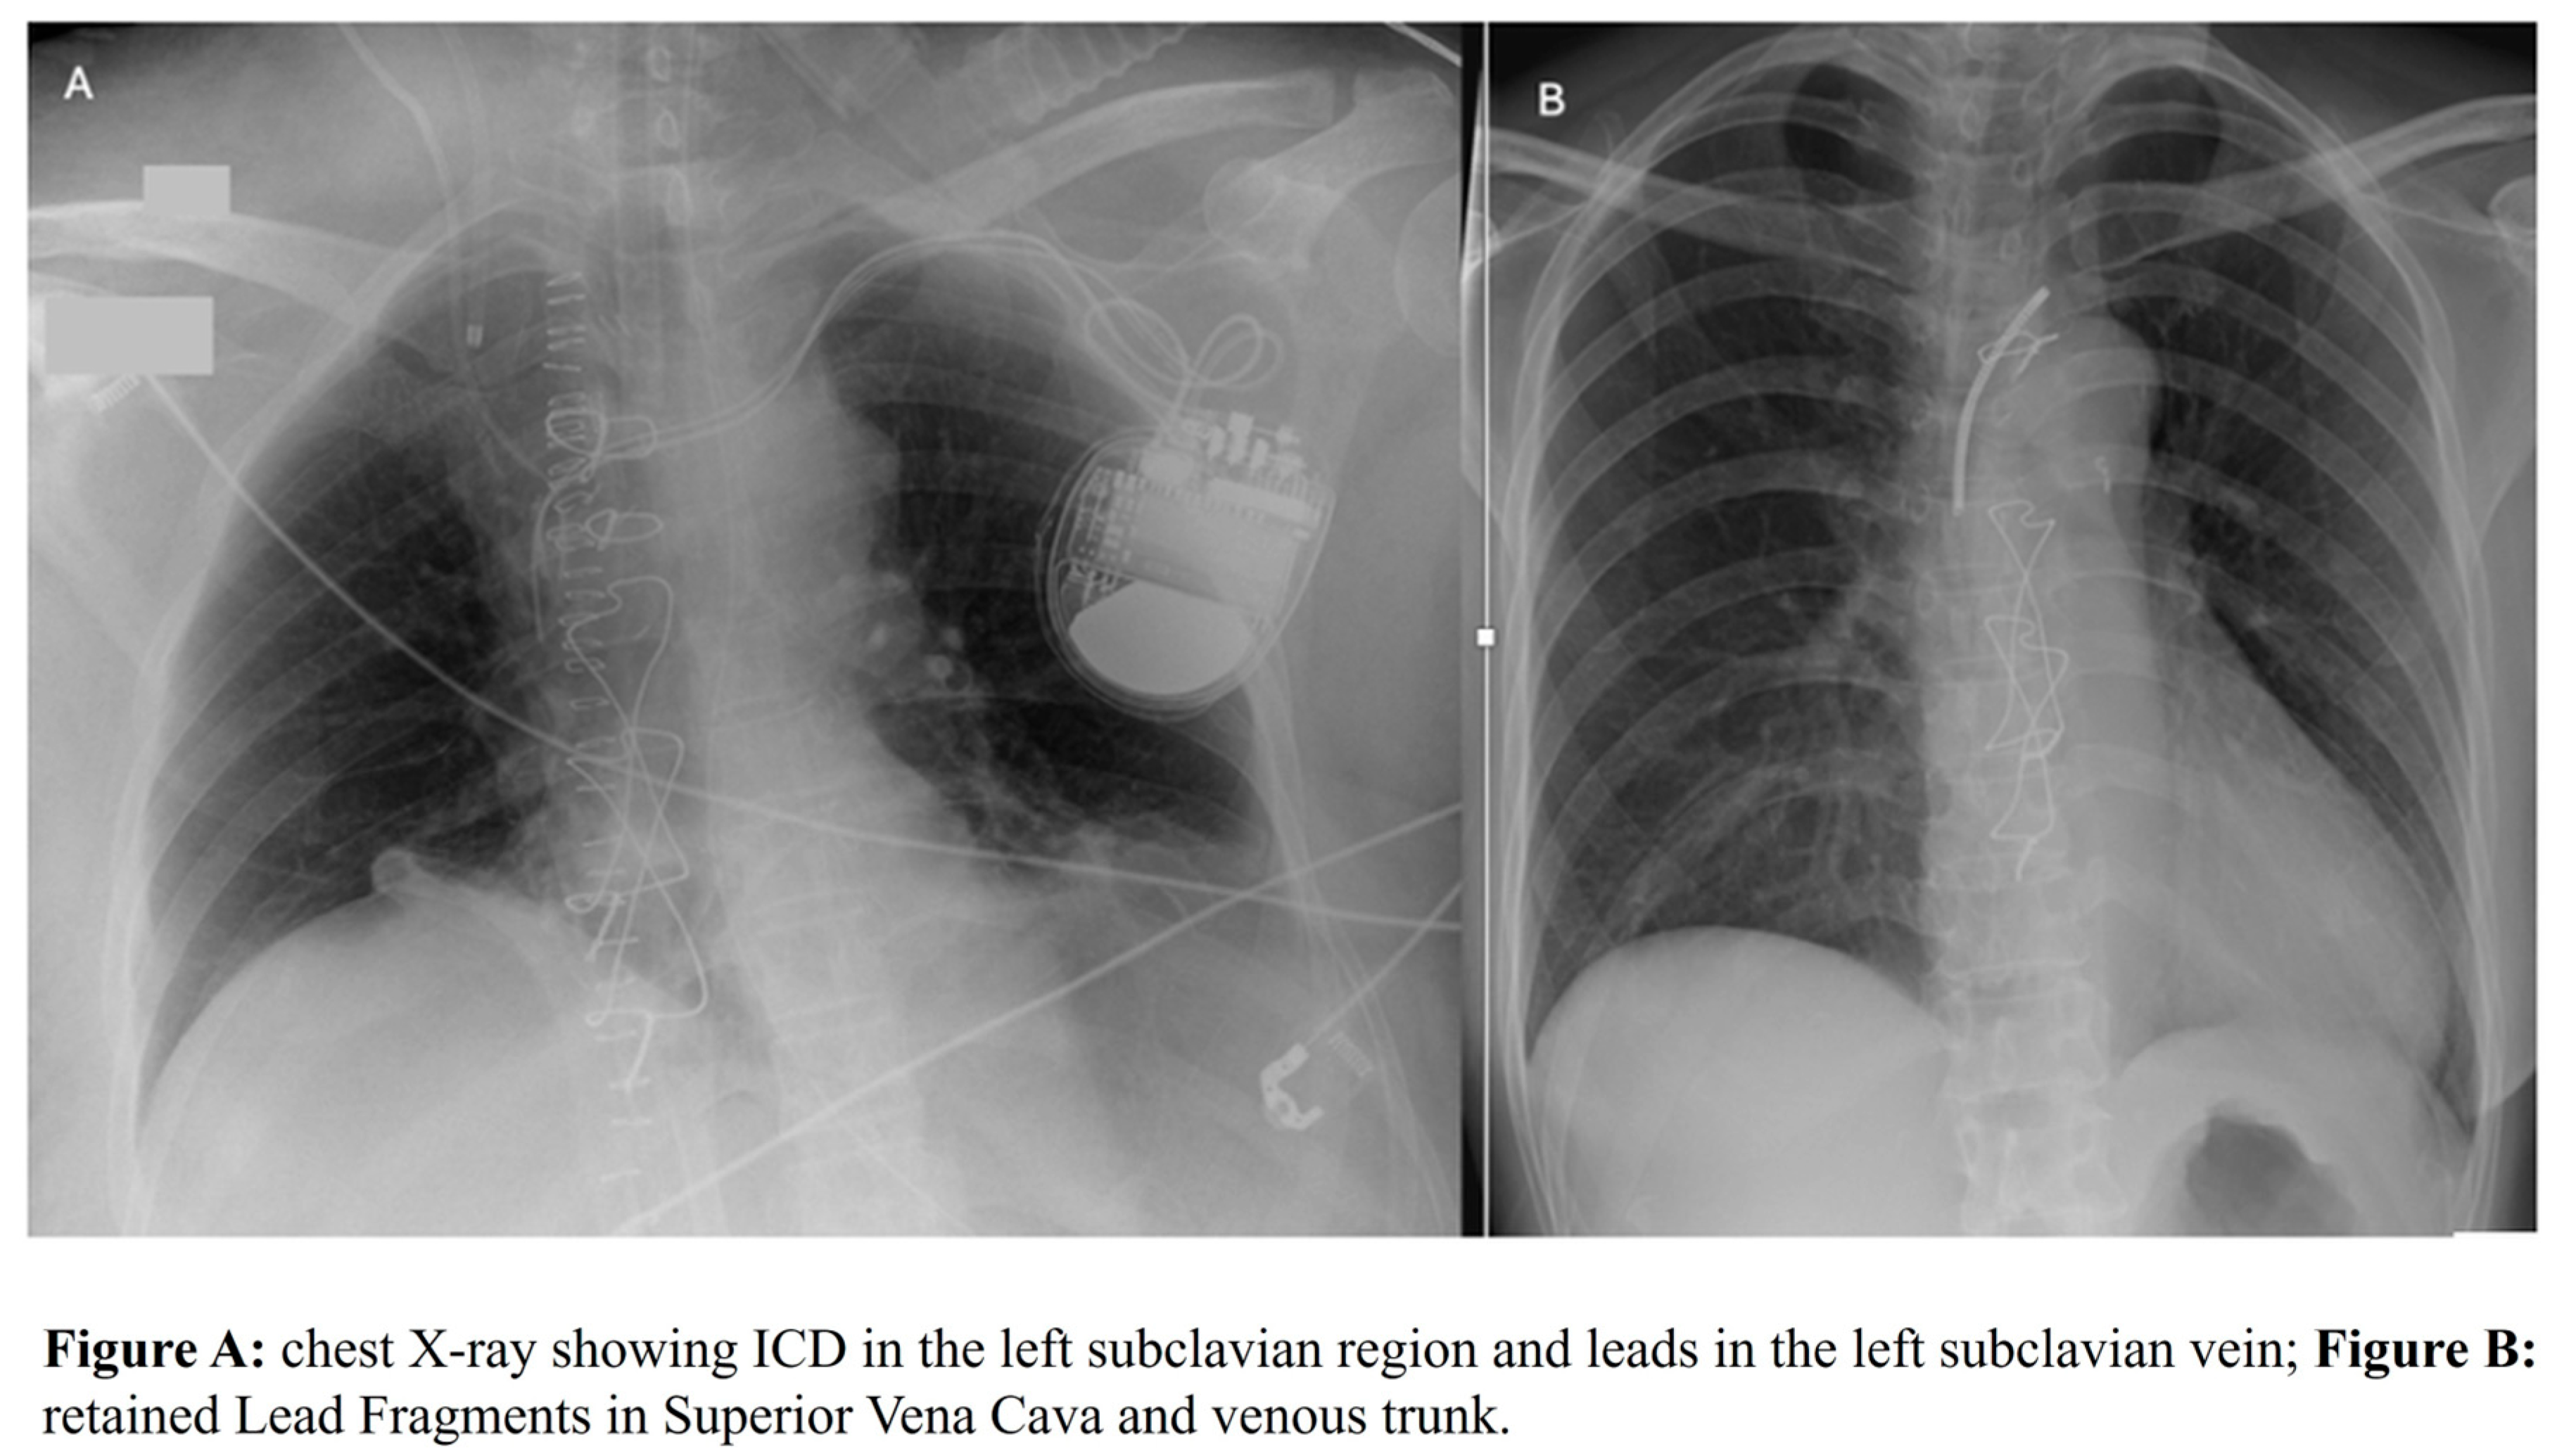

Retained Lead Fragments in Superior Vena Cava and Early Post-Transplant Outcomes: A Single Center Preliminary Retrospective Study